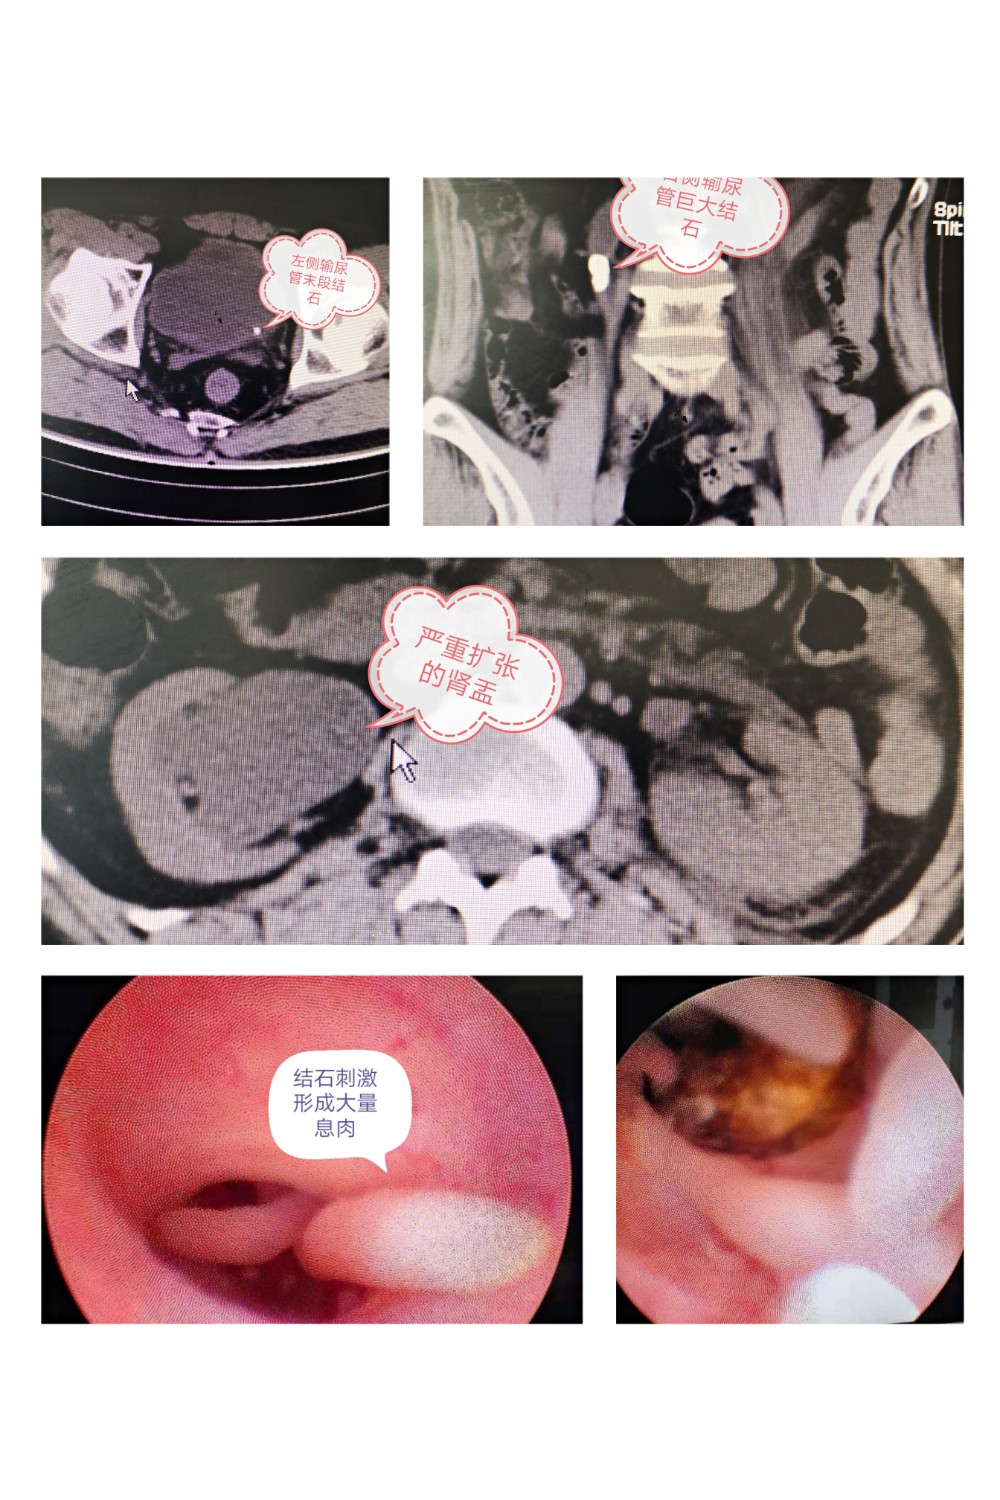

近日,郑州市第九人民医院泌尿外科收治一例双侧输尿管结石的病人,患者男性,57岁。患者因突发左侧腰腹部疼痛3个小时入院,入院后完善检查提示除了左侧输尿管末段结石外,右侧输尿管上段有一巨大结石(约2.5cm),右肾重度积水,肾实质变薄,患者并无右侧腰腹部疼痛等任何不适。

积极术前准备后,郑州市九院泌尿外科张科庄副主任医师当天给患者安排了手术。术中顺利处理了左侧输尿管结石,右侧输尿管结石周围可见大量息肉形成,包裹结石,这种情况多见于结石梗阻较久,如果继续应用钬激光完成手术并不难,但术后极易形成狭窄。经过再三考虑后决定要置入输尿管支架管保护右肾功能,后期行腹腔镜输尿管切开取石术。手术顺利,患者双肾功能得以保护。